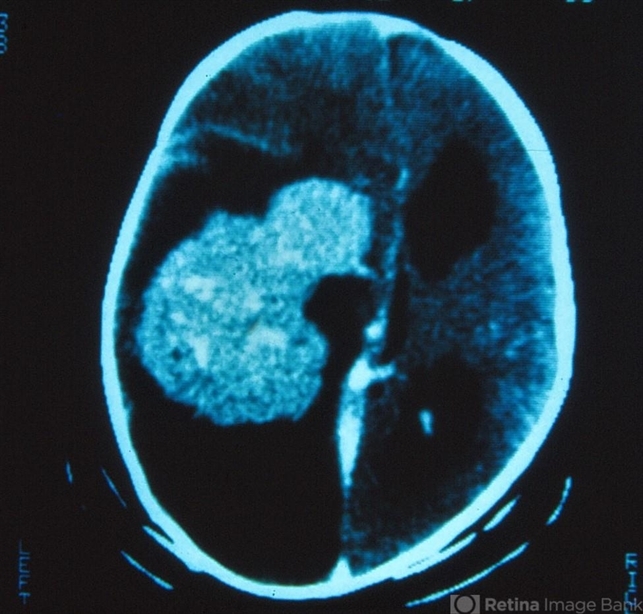

Choroidal Plexus Carcinoma of the Brain

Choroid Plexus Carcinoma of the Brain

A 3-month-old boy was noticed to have a pupillary reflex on his left eye. A diagnosis of bilateral retinoblastoma was made and the left eye was enucleated. The small tumor on the right eye was treated with radiation. Imaging of the brain revealed a tumor in the region of the choroid plexus consistent with a choroid plexus carcinoma. A removal of the brain tumor was attempted.